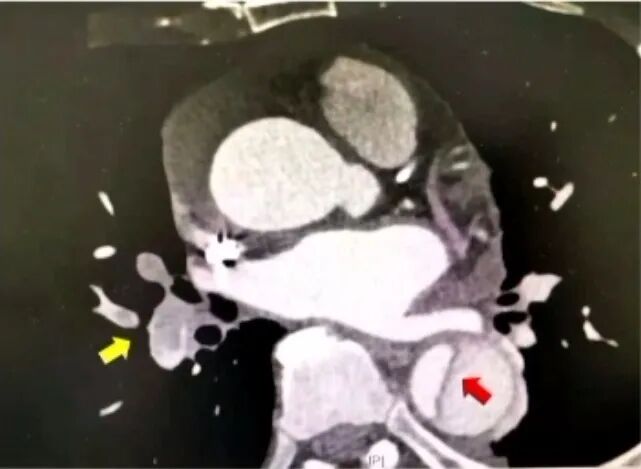

急性心肌梗死(AMI)、急性肺栓塞(APE)和急性主动脉夹层(AAD)是急性胸痛的三大常见病因,且属于高危胸痛。遇到急性胸痛患者,应首先考虑这三大病因。D-二聚体对上述三种疾病的诊断和鉴别具有重要价值。

D-二聚体用于急性主动脉夹层诊断